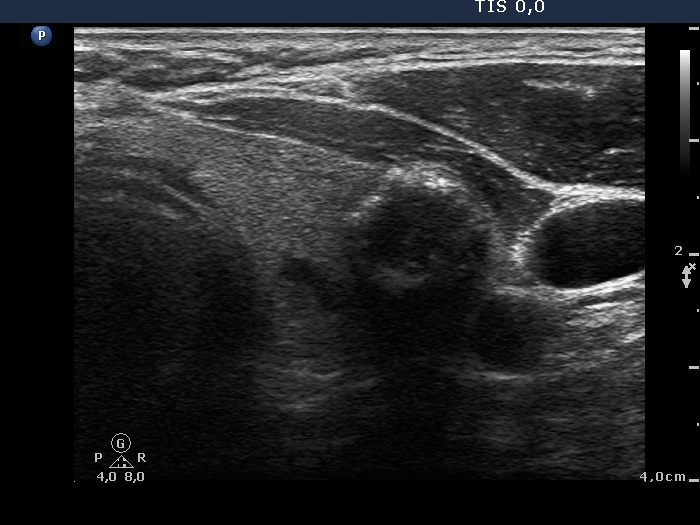

Benign colloid goiter (cytological diagnosis) |

There is a calcification in the dorsal part of the lesion.